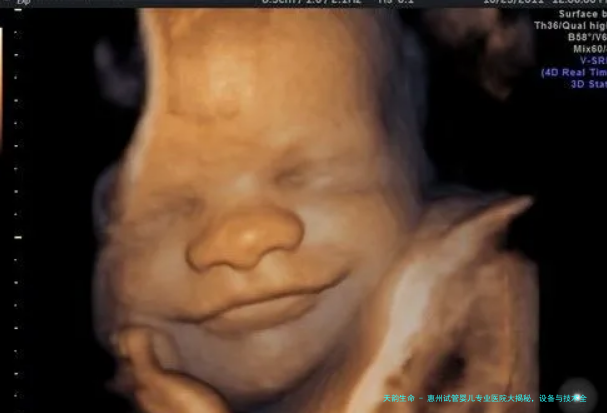

这家医院多年来一贯致力于试管科与试管婴儿治疗范围的研讨与前行。作为本地非常具有影响力度的公立医院,其所在试管婴儿技术远近享誉,不但在广东省内取得认同,在周围地域也颇具名誉。医院配置了诸多先进设备,像尖端的胚胎培育系统、人授及胚胎移植配备等,能够依照病患的不怜悯况,量身定制个体化的治疗计划,在试管婴儿临床治疗方向经验实足。

起先,其收集的用的胚胎培育系统十分尖端,使用专业的培育液,并模仿出恒温度的培育环境,为胚胎的健康发育缔造了近乎完备的前提,大大提高了试管婴儿的成功率。